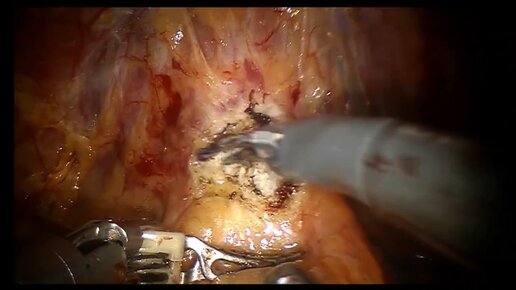

Робот-ассистированная нервосберегающая простатэктомия по поводу рака простаты

Денис Давыдов врач-уролог, онкоуролог